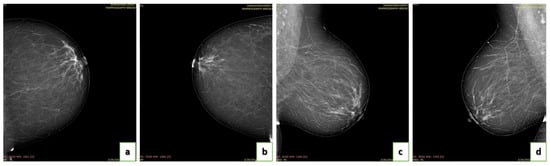

4.4. Breast Density

- A (0–25%): Almost entirely fatty indicates that the breasts are almost entirely composed of fat. One out of ten women has this result.

- B (25–50%): Scattered areas of fibroglandular density indicate some scattered areas of density, but most of the breast tissue is non-dense. Four out of ten women have this result.

- C (50–75%): Heterogeneously dense indicates that there are some areas of non-dense tissue but that most of the breast tissue is dense. Four out of ten women have this result.

- D (75–100%): Extremely dense indicates that nearly all breast tissue is dense. One out of each women has this result.